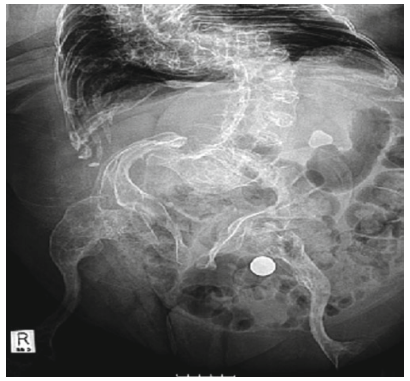

Nếu nhiều hơn 2 mảnh sỏi nằm trên niệu quản và dẫn đến tắc nghẽn thận thì được gọi là chuỗi sỏi (steinstrasse). Thông thường 1 mảnh sỏi lớn sẽ gây tắc nghẽn niệu quản trước, sau đó những mảnh sỏi sau sẽ mắc kẹt ở phía trên.

10

Hình 10.Chuỗi sỏi niệu quản phải đoạn chậu sau TSNCT

ở bệnh nhân mang sỏi san hô được điều trị kết hợp TSNCT và LSTQD

Nguyên nhân dẫn đến chuỗi sỏi thường là do kích thước viên sỏi ban đầu lớn, vì vậy những viên sỏi > 2,5cm đều được khuyến cáo là không phù hợp với TSNCT.

Vị trí chuỗi sỏi thường gặp nhất là niệu quản đoạn xa (64%), kế đó là đoạn gần (29%) và cuối cùng là đoạn giữa (8%).